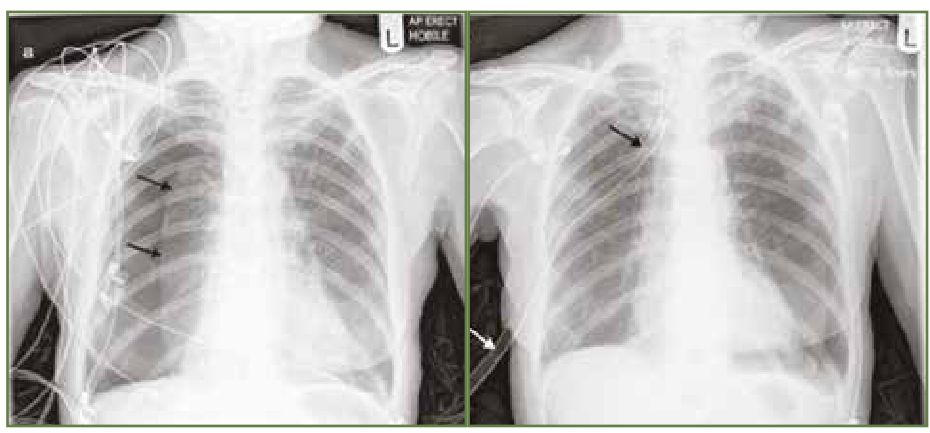

Na Európskom rádiologickom kongrese prezentoval P. Bielik v júli tohto roku metódu, ktorá umožňuje lekárom pomocou strojového učenia stanoviť presnú diagnózu choroby z röntgenových snímok, a tiež spôsob, ako jeho firma dokáže analyzovať, či strojové učenie funguje správne. Firma LatticeFlow patrí v tejto oblasti medzi najlepšie na svete.

Hlavný problém, ktorý rieši skupina vedcov a inžinierov v LatticeFlow, je robustnosť a bezpečnosť systémov založených na strojovom učení. V praxi to znamená, že vyvinuli softvér ktorý sa usiluje porozumieť tomu, čo sa neurónová sieť naučí, s cieľom zabrániť chybám pri spracovaní nových dát – aby sa napríklad pacientovi neurčila diagnóza z nesprávnej interpretácie pri rozpoznávaní obrazu na röntgenovej snímke.